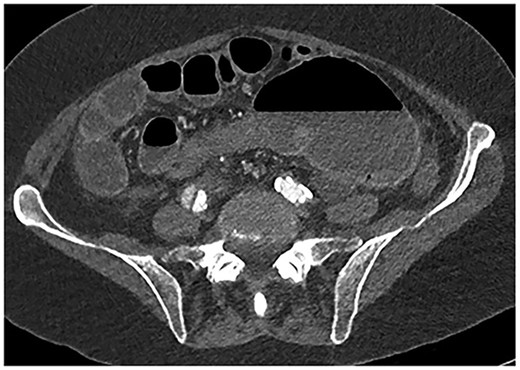

A 61-year-old female with known Marfan Syndrome was admitted to the emergency department with 3-day history of abdominal pain, nausea, vomiting and bowels not opening. Past medical history included three previous episodes of Type A aortic dissection, recent aortic root and ascending aorta replacement alongside bioprosthetic aortic valve replacement. She was an ex-smoker and usually independent at home. On presentation, the patient was haemodynamically stable and apyrexial. Biochemical results were unremarkable except for a Lactate dehydrogenase (LDH) of 309 and a C-reactive protein (CRP) of 101. On examination, she had a diffusely tender and distended abdomen, without signs of peritonism. An erect chest X-ray shows left pleural effusion with a dilated aortic root (Fig. 1). A computed tomography (CT) of thorax, abdomen and pelvis was requested, which demonstrated a caecal volvulus with a dilated cecum of 8.8 cm and upstream small bowel dilatation with air fluid levels, and a chronic aortic dissection extending from the ascending thoracic aorta to the common iliac (Figs 2–4). Following consultation between radiologists, cardiothoracic surgeons and general surgeons, she underwent an emergency laparotomy and right hemicolectomy with side-to-side ileocolic anastomosis. Intraoperatively, the caecal volvulus, comprising a dilated ascending colon measuring up to 10 cm, was delivered and resected along with its mesentery. The patient was admitted to the intensive care unit post-operatively for close blood pressure monitoring and control and stepped down to level 3 wards on day-2 post-operation. Her operation was complicated by a small infected wound haematoma thatwas managed with a 5-day course of ciprofloxacin. A CT of the abdomen and pelvis to investigate a rising CRP on day-9 revealed a subcapsular liver haematoma thath was managed conservatively. The patient was discharged 12-days post-operatively. Histology from the resected colon showed evidence of ischaemia in keeping with a closed loop obstruction such as caecal volvulus. There was also an incidental T1 N0 colonic tumour arising from a sessile serrated polyp and two other serrated polyps. A colonoscopy to inspect the remaining colon has been arranged.

Fluid-filled mid to distal appendix with some gas in the proximal part outlined with yellow arrows. Appendix is seen within the upper abdomen, indicating an increased likelihood of caecal volvulus.